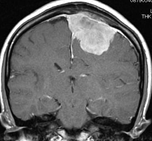

上矢状静脈とは、頭の中央を走行する太い静脈です。その静脈の壁に接した硬膜から発生する髄膜腫は、無症状のこともありますが、腫瘍のサイズが大きいと手足の運動を司る場所(中心前回と言います)が圧迫を受けるために麻痺やけいれんを生じることがあります。

(術前MRI)

(術後MRI)